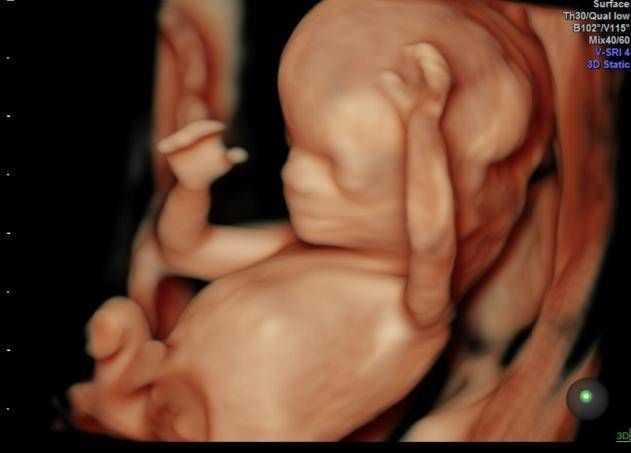

孕期产检,相信不少孕妈妈都很期待四维排畸这一项了,四维彩超排畸检查有不少准妈妈也想带着准爸爸进去,一同分享这其中的喜悦。

【 医生|为什么有些医院做四维彩超不让家属陪同这些原因,大家有权知道】小茹怀孕24周左右的时候,身边朋友提醒她这个时候需要做四维大排畸了,不仅能知道胎宝宝发育状况,还可以提前看到宝宝的长相。

3、保护胎儿的性别:四维检查会检查出胎儿的性别,而且胎儿性别是孕妈及家人最关心的一件事。如果家属入内,有的出于好奇,有的出于性别选择,都会询问医生胎儿的性别。而医生鉴定胎儿性别如果不是医学上需要的,这是违法的,所以医生不会去触碰这个红线,家属不论怎么询问,医生都会保护好胎儿性别。